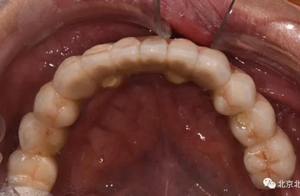

圖十四:口內(nèi)照

圖十六:術(shù)后三個(gè)月永久修復(fù)取模,夾板固定。

圖二十五:口內(nèi)照。